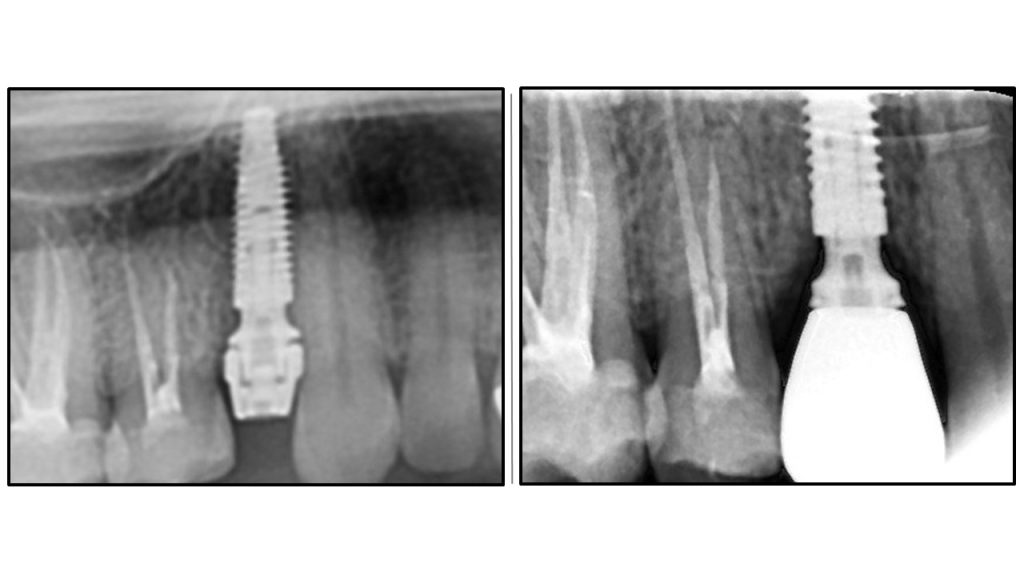

immediate implant placement with oaot

Immediate placement with one abutment one time still yields the same results

Clinical application of these protocols is performed daily at White Clinic Belgrade